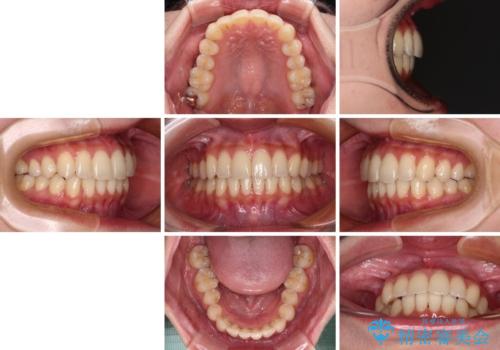

- 前歯のデコボコと強い咬みしめを気にして来院された患者様です。

インビザラインを用いて、前歯の叢生を解消するとともに、ディープバイトを改善していくこととしました。

海外へ転居する予定があったため、1日22時間以上の装着時間をしっかりと守っていただき、予定期間よりも早く、思っていた以上にきれいに仕上げることができました。